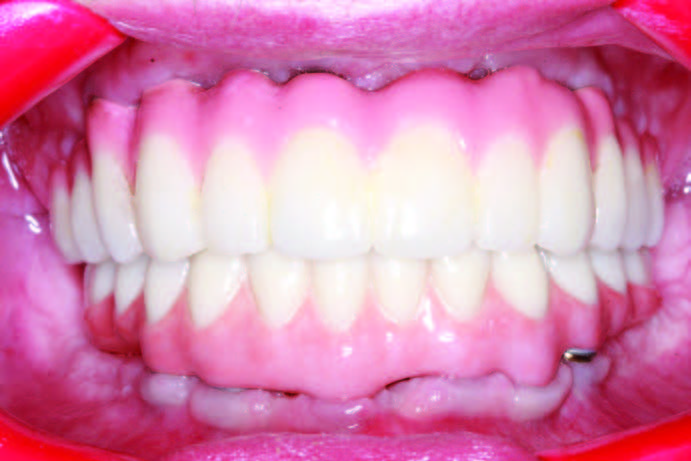

In evaluating the mandibular PMMA provisional, it was noted that there were ridge-laps in the intaglio, which would lead to food impaction, decreased hygiene, and increased risk for peri-implant mucositis and peri-implantitis, in turn leading to premature failure (Figure 16). A new PMMA was ordered, and the intaglio was hand-carved and returned to the lab team to be rescanned and refabricated. This case required 4 PMMAs to improve on overbite, overjet, phonetics, and cleanseability (Figure 17).

The ability to work out aesthetics and phonetics and test function prior to the finalization of prostheses cannot be understated. The final Obsidian fused-to-gold bridge (Glidewell Dental Laboratories) opposing a Monolithic BruxZir hybrid prosthesis mimics the prototypic restoration as confirmed with the PMMAs (Figure 18). The intaglio demonstrates the time, effort, and attention required to produce sluiceways that will facilitate the use of an oral irrigator and a proxy brush (Figure 19).

The retracted view and the patient’s full-face smile are demonstrative of the excellent laboratory communication and careful attention to each step in this patient’s journey (Figures 20 and 21). His oral care required extra attention due to his emotional and psychological deficits caused by his hydrocephaly. While dentists cannot guarantee the longevity of prostheses, the journey from this patient’s beginning to his new oral restorative beginning creates hope and changes interpersonal feelings and responsibility. The implant placement and number should allow for optimal mastication throughout his life with proper maintenance and homecare (Figure 22).